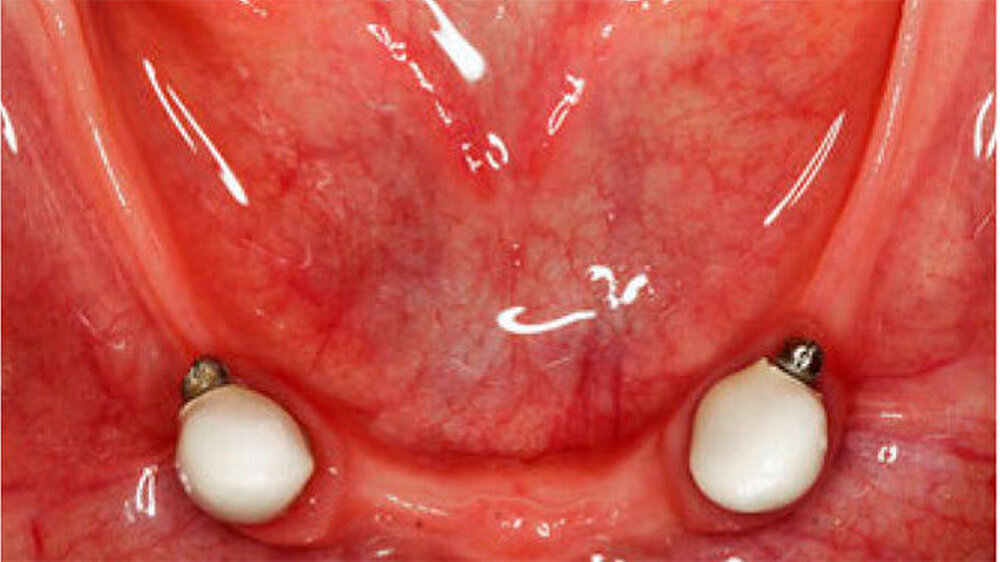

Aufgrund des anatomisch sehr ungünstigen Prothesenlagers war der Erhalt der Restbezahnung im Oberkiefer anzustreben. Nach Kariesexkavation und Wurzelkanalbehandlung konnten beide Zähne mit einer Wurzelstiftkappe versorgt und die alten Prothesen entsprechend umgebaut werden. Im Anschluss an die Meisterabformungen und an die Ausrichtung der Wachswälle wurden die Modelle schädelbezogen einartikuliert, und die Prothesenzähne nach ästhetischen und funktionellen Richtlinien aufgestellt. Eine bilateral balancierte Okklusionsbeziehung konnte umgesetzt werden. Im Oberkiefer wurde eine gerüstverstärkte Totalprothese hergestellt, die auf den beiden Wurzelstiftkappen 16 und 26 verankert war. Im Unterkiefer konnte die Patientin mit einer Totalprothese versorgt werden (Abb. 21 bis 23).

Im Falle einer gewünschten Korrektur der mikrognathen Maxilla wird eine Umstellungsosteotomie notwendig. Zur Komfortsteigerung ist im Oberkiefer eine implantatretinierte, gaumenfreie Rekonstruktion (abnehmbar oder bedingt abnehmbar) anzustreben. Voraussetzung ist eine vorgängige Optimierung des Knochenbetts mittels Sinusbodenelevation in Kombination mit einem autologen Knochenblocktransplantat. Im Unterkiefer scheint aufgrund des geringen Knochenangebots und der fehlenden Hart- und Weichgewebe die Versorgung mit einer Hybridprothese, retiniert auf interforaminalen Implantaten, adäquat.